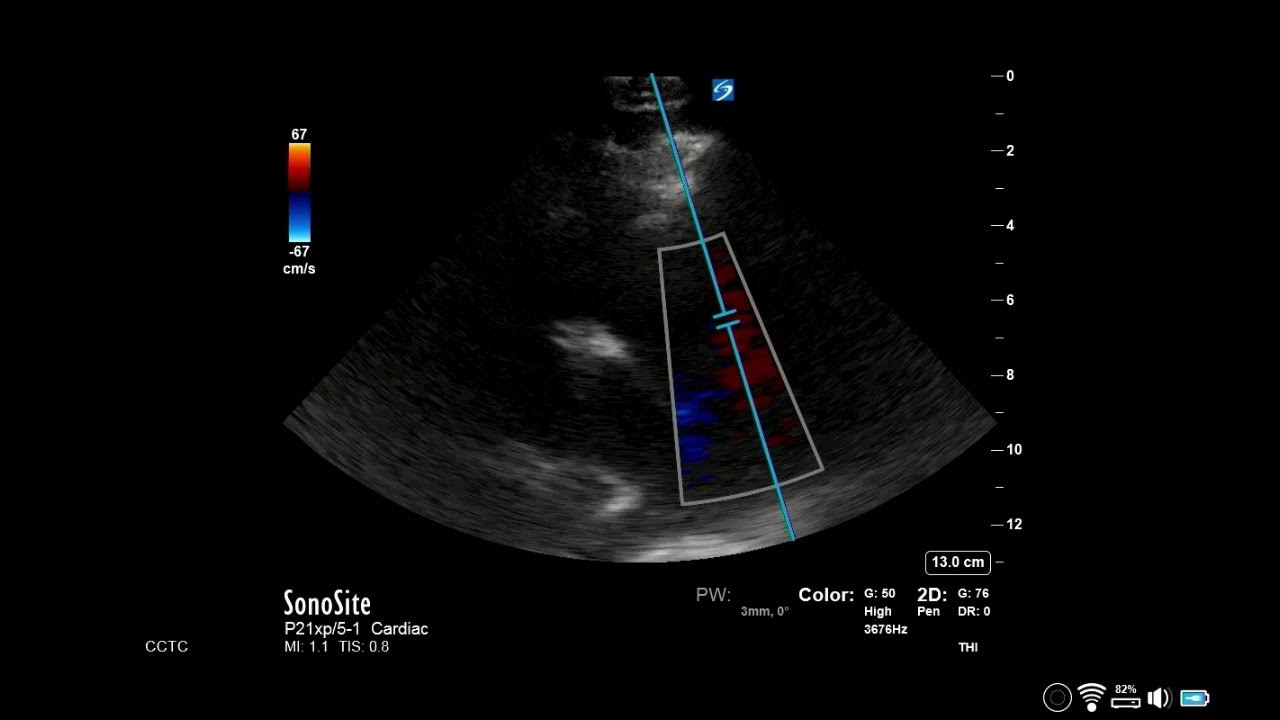

From www.youtube.com

How to estimate RVSp using TR jet? YouTube How To Find Rvsp The gold standard way for obtaining the right ventricular systolic pressure (rvsp) and the pulmonary artery pressure is an invasive test called a heart catheterization. It is based on measuring the tr jet. Can be difficult to assess. Right ventricle systolic pressure (rvsp) is a measurement commonly found on an echocardiogram that provides us a value. The right ventricular systolic. How To Find Rvsp.